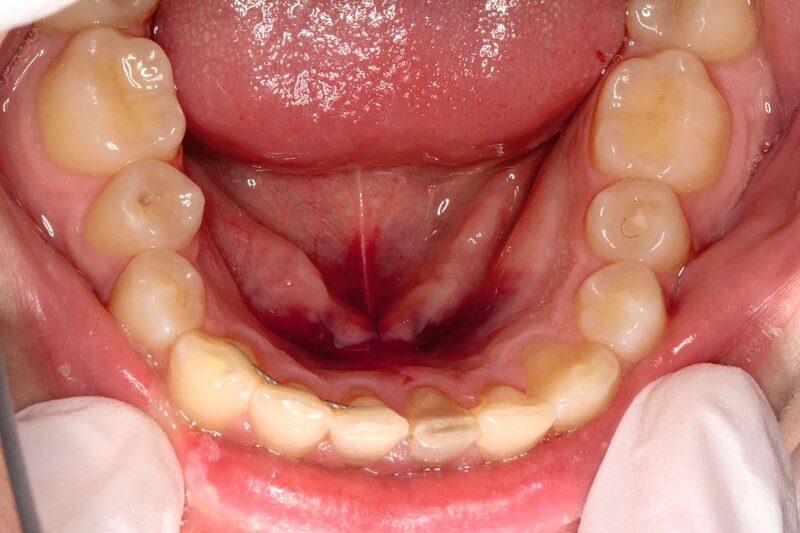

Zusätzlich zeigten sich ein dunkel-bläuliches Hämatom sublingual in Regio 32 bis 42 und ein korrespondierendes Hämatom im Vestibulum zwischen den Zähnen 31 und 41 (Abbildungen 1 und 2). Beide schienen mit der extraoralen Kinnwunde zu korrelieren und waren auf Palpation schmerzhaft. Es konnten keine Stufen ertastet und keine Krepitation wahrgenommen werden (Flowcharts Abbildungen 13 und 14).